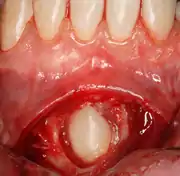

Pericoronitis is an infection of the soft tissue that covers the crown of an impacted tooth and is usually caused by the normal oral microbiota. For most people there exists a balance between the host defenses and the oral micriobiota but if the host defenses are compromised like during minor illness such as influenza or an upper respiratory tract infection, pericoronitis results. Another common cause is entrapment of food beneath the gum flap (also called an operculum). Pericoronitis can present as a mild infection or severe infection. In its mildest form it is just a localized tissue swelling and soreness whereas in severe forms the swelling is slightly larger even sometimes creating trismus (difficulty opening the mouth).

Sometimes, a surgeon may wish to expose the canine for aesthetic purposes. This may be achieved through open or closed exposure. Studies show no advantage of one method over another.[11] A laser can be used to uncover superficially impacted teeth with no bleeding and quick recovery.[12][13][14]